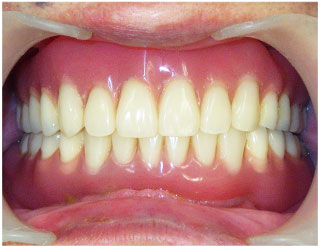

この方は奥歯が欠損した状態でご来院されました。

入れ歯は入れたくないというご希望でしたのでインプラントをお勧め致しました。

インプラント治療の他に、下の歯の銀歯も白くしたいという事でしたので

銀歯を白いセラミッククラウンにする治療も一緒に行いました。

ご予算をなるべく抑えて治療したいという事でしたので

右は2本のインプラントを入れて3本分の歯を入れて治しています。

この様にインプラントは欠損している歯の本数分が必要なわけでは無く、

インプラントでブリッジをして治す事が多々あります。

当院では患者様のご予算に応じた治療プランのご提案を行っております。